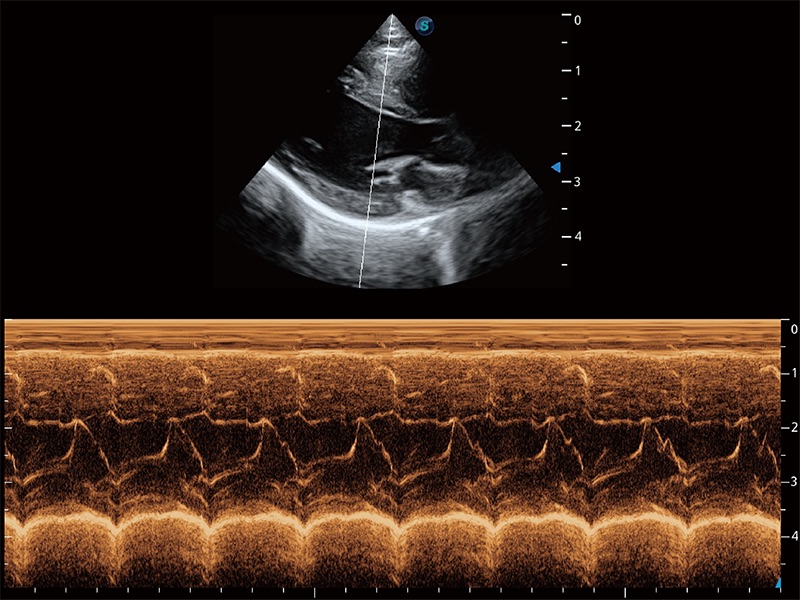

• AMM 解剖M型

通过360度任意调节3条M型取样线,在同一心动周期上观察心脏不同位置的运动曲线,得到准确的心功能测量数据,有效评估心肌运动及左心室功能。